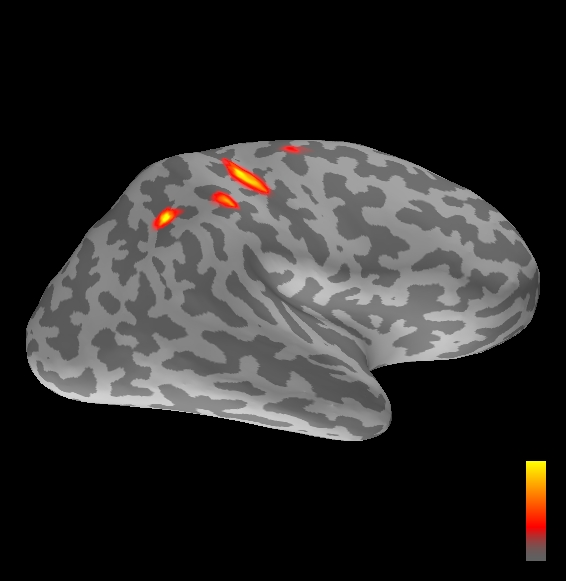

5.2 Results

We applied the ASMC sampler to MEG topographies taken from the above recordings by selecting specific time points according to the previous analysis; the parameter values in the algorithm were the same as those used for the analysis of synthetic data, with the only exception of the noise standard deviation , here estimated from the pre–stimulus interval. In order to validate the results of the ASMC, we also computed source estimates using three other methods: a PF, that approximates the posterior distribution for the current dipoles conditioned on the data up to the selected time point; dSPM, which is based on a distributed source model with an –prior, and consists in normalizing the Tikhonov regularized solution by the noise standard deviation; and sLORETA, which is similar to dSPM but is claimed to have a smaller localization bias. Figure 4 shows the results at , and ms after the stimulus onset. The results are visualized on a computer representation of the brain obtained by “inflating” the cortical surface: gray levels contain the anatomical information, light gray representing gyri and dark gray representing sulci; the activity estimate is coded in color scale, increasing from red to yellow. Importantly, this visualization allows activity in the sulci to be clearly visible; on the other hand, since neighbouring volumes may be moved apart by the inflation process, distinct activity regions are often due to underlying volumetric masses that are very close to each other.

Before describing the results, let us comment on the qualitative difference between the images produced by the ASMC sampler and the PF, on the one hand, and those produced by dSPM and sLORETA, on the other. First of all, we point out that all the quantities shown in the images of Fig. 4 are somehow related to the probability of activation at specific locations. Indeed, for both the ASMC and the PF we plot the approximation of the intensity measure (3.8); for any single grid point, this value can be interpreted as the probability of a dipole being at that location, while it integrates, over a given volume , to the mean number of dipoles within . As for dSPM, the represented quantity is a statistical value that is –distributed under the null–hypothesis of zero activity; as a direct consequence, it also yields a probability of activation, which is however not constrained to be dipolar. Similar considerations apply to sLORETA, although with a different statistical distribution. Importantly, the representation of the results is clearly affected by the setting of the visualization threshold. Owing to the explained differences between the methods, it seems reasonable to use a different value for each method. At the same time, since the plotted quantity is a probability of activation, it seems right to use the same thresholding for different time points. In this connection, the thresholds in Fig. 4 have been chosen by hand following the guidelines just outlined.

Using the same thresholding and parameters at different time points makes the four methods respond differently to the diverse intensities of the different sources. Whenever a stronger source is active, both sLORETA and dSPM will tend to produce widespread estimates, while weaker sources will be represented as small active areas. The behaviour of the ASMC and of the PF is the opposite: a stronger signal will lead to a precise localization of a dipolar source, and then to a focal marginal distribution for the location; a weaker signal will translate to higher uncertainty on the source position, and therefore a more widespread posterior map.

At ms, the ASMC localizes two sources, one in the right hemisphere and a weaker one in the left hemisphere; these sources appear to be compatible, for timing and location, with the Posterior Parietal Contra and Parietal Opercular Ipsi described in Mauguiere et al. (1997). The PF finds the very same source in the right hemisphere, but it estimates no dipoles in the left one. Such discrepancy between these two methods, which are based on the same source model, is possibly due to two facts: first, thanks to its iterative nature, the ASMC is likely to explore the state space more thoroughly and is therefore more suited to identify weak sources; second, the log–uniform prior on the strength of the dipole moment in the ASMC has a wider range than the corresponding Gaussian prior in the PF. Slightly different results are provided here by dSPM and sLORETA. The activity estimate computed by dSPM seems very similar to that of ms, having the same spatial distribution with a weaker intensity. The estimate of sLORETA in the right hemisphere includes that of the ASMC and of the PF. Neither dSPM nor sLORETA find significant activity in the left hemisphere.